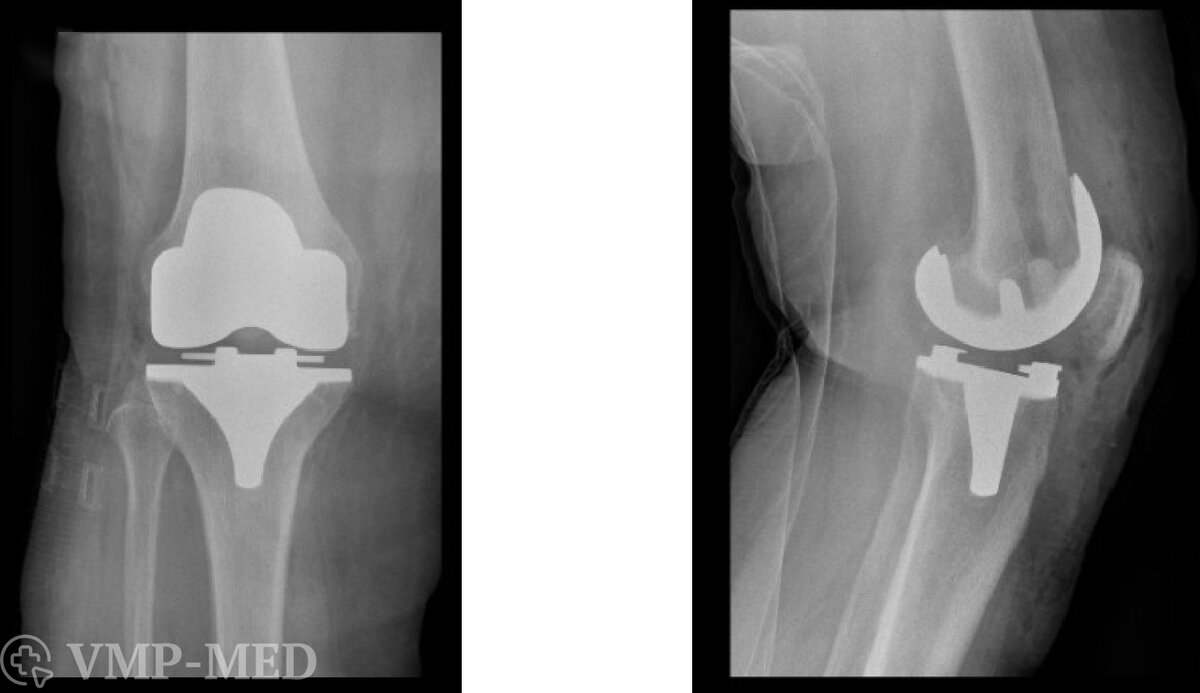

В области эндопротезирования коленного сустава существует несколько основных методик и технологий. Тотальное эндопротезирование коленного сустава (ТЭКС) является наиболее распространенным типом операции, при котором заменяются все три компонента коленного сустава: бедренная, голеностопная и чашеобразная кости. Этот тип операции обычно рекомендуется для пациентов с продвинутым артрозом или другими серьезными заболеваниями суставов.

Есть также частичное эндопротезирование коленного сустава, при котором заменяется только одна или две части коленного сустава, сохраняя как можно больше здоровой кости и хряща. Это может быть хорошей альтернативой для пациентов с менее серьезным повреждением сустава. Ревизионное эндопротезирование коленного сустава предназначено для замены существующих искусственных суставов, которые могли бы износиться или повреждаться со временем. Это более сложная операция, чем первичное эндопротезирование, и часто требует специализированных навыков и технологий.

Виды эндопротезов

Эндопротезы коленного сустава бывают различных видов, и их конструкция и материалы могут значительно варьироваться. Основные материалы, используемые для изготовления эндопротезов, включают металл, керамику и пластик. Металлические компоненты обычно изготавливаются из высокопрочных сплавов, таких как титан или нержавеющая сталь, и обладают долговечностью и высокой устойчивостью к износу. Керамические компоненты также демонстрируют хорошую устойчивость к износу и могут обеспечить более гладкое скольжение суставных поверхностей. Пластиковые компоненты, обычно изготовленные из высокомолекулярного полиэтилена, могут служить в качестве подушечек между металлическими или керамическими компонентами, минимизируя трение и износ.

Существует несколько основных конструкций эндопротезов коленного сустава. Тотальные эндопротезы предназначены для замены всех поврежденных частей коленного сустава, в то время как частичные эндопротезы заменяют только определенные области. Некоторые эндопротезы разработаны так, чтобы имитировать естественную анатомию и движение колена, в то время как другие могут иметь более упрощенную конструкцию. Важным фактором является выбор между цементными и бесцементными эндопротезами. Цементные эндопротезы закрепляются с помощью специального костного цемента, что обеспечивает немедленную фиксацию, в то время как бесцементные эндопротезы разработаны так, чтобы кость могла прирасти к имплантату со временем, создавая более естественное и долгосрочное соединение.